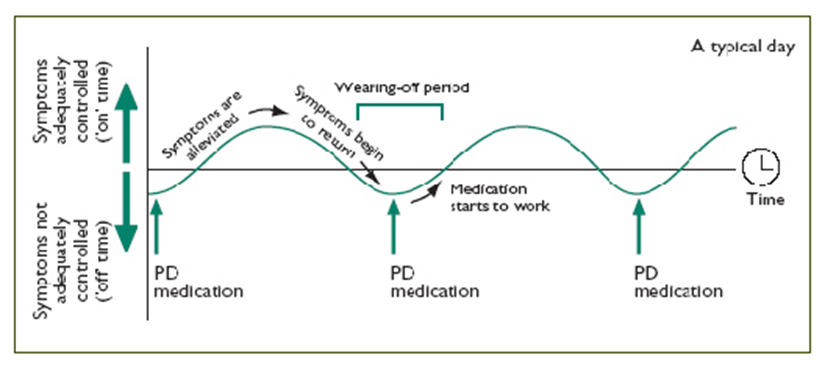

What is the “ON-OFF” phenomenon?

As PD progresses, patients may experience “ON-OFF” periods.

“OFF” periods are times when dopamine levels are low in the brain, and when the medicine is wearing off or not felt when it should be, presenting as motor or non-motor fluctuations. While “ON” periods are those when the patient doesn’t experience any motor (or non-motor) fluctuations and the effects of medications are good.